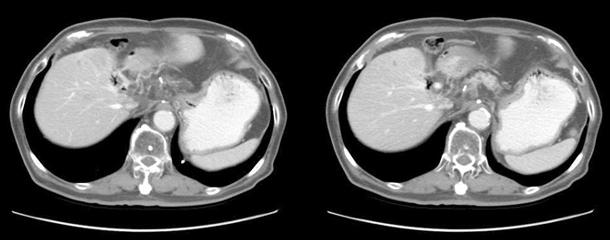

The response of radiotherapy was remarkable and on 18F-FDG PET/CT scan, there was no increased FDG uptake on the metastatic node at 3.5 month from the end of radiotherapy (Fig. 3) and on abdomen CT scan, it was completely disappeared at 12 months from radiotherapy. There was no evidence of recurrence until 3.5 years follow-up (Fig. 4).

Fig. 4. Abdominal CT scan at 36 months after radiotherapy. At last follow-up, there was no evidence of loco-regional recurrence or distant metastasis.